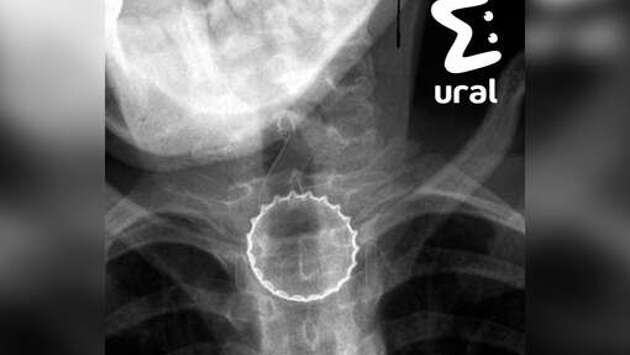

В Челябинске 16-летний подросток случайно проглотил железную крышку от бутылки, ему потребовалась срочная операция. Об этом сообщает Telegram-канал Ural Mash. По информации Telegram-канала, инцидент произошел, когда несовершеннолетний ловил металлическую крышку губами. Предмет попал ему в горло и застрял в пищеводе. Медики заключили, что подростку требуется срочная операция в связи с тем, что крышка имела острые края, которые могли порезать внутренние органы несовершеннолетнего. Хирурги провели подростку операцию, она прошла успешно. Сообщается, что сейчас пациент уже находится дома. Его посадили на диету. До этого в Новосибирске врачи извлекли из 19-летней девушки два килограмма волос и спасли ее. Выяснилось, что россиянка страдает синдромом Рапунцель. Она три года ела собственные волосы, пока они полностью не заполнили желудок.